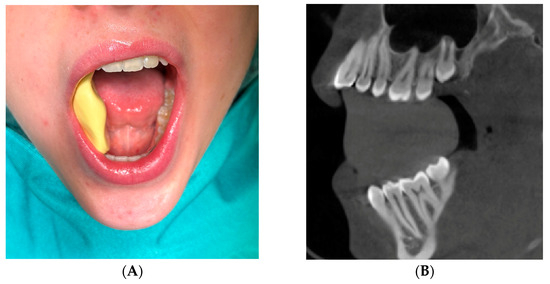

2.3. Clinical Patients

2.3.1. Eligibility/Inclusion Criteria